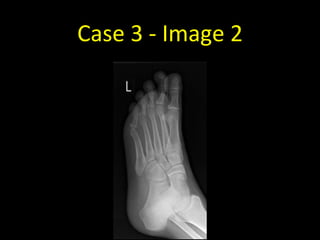

Case 3 - Image 2

Case 3

• Frontal and oblique

radiographs of the left foot

• There is a minimally displaced

transverse fracture of the

distal shaft of the left third

proximal phalanx

• Note how difficult it is to see

the fracture on the frontal

projection (it’s just about

visible as a transverse dense

line)

• This is why we need two

views when assessing for

fractures

• In this case the projections

are frontal and oblique - the

projections aren’t necessarily

always at right angles to each

other